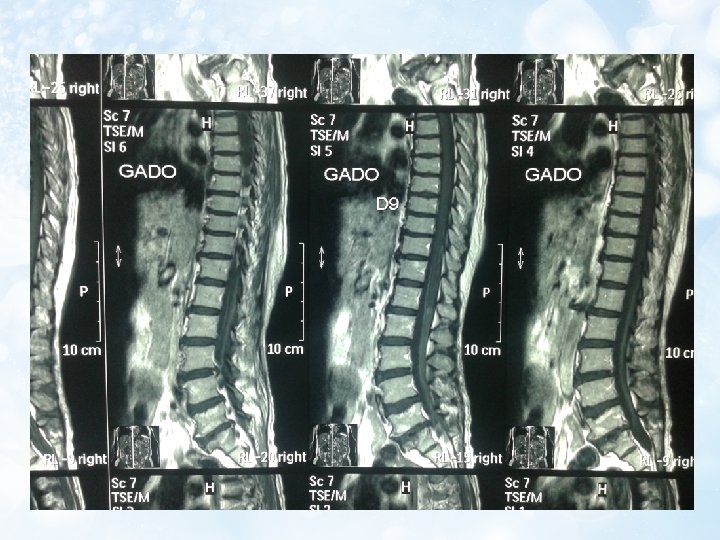

6. MRI Thoái hóa đốt sống thắt lưng và đĩa đệm L 3/4, L 4/5, L 5/S 1 Thoát vị đĩa đệm L 5/S 1 trung tâm chèn ép bao màng cứng và chèn rễ thần kinh cũng mức 2 bên Thoát vị Schmorl S 1 Tủy bám thấp, theo dõi viêm tủy cắt ngang D 11 L 2

b. Chẩn đoán phân biệt tổn thương do chèn ép hay do viêm: -Sự giảm tín hiệu xung T 1 và tăng tín hiệu xung T 2 trên MRI (hình ảnh) -Dựa trên lâm sàng Dấu chứng Khởi đầu Triệu chứng bắt đầu Chèn ép tủy Từ từ O Đau kiểu rễ, diện chèn X ép giảm mất cảm giác Viêm tủy Đột ngột Nhiễm trùng X O Diễn biến Liệt co cứng nhiều O Liệt mềm-cứng X Dịch não tủy Phân ly đạm tế bào O Protein và tế bào tăng O -Trên MRI đồng thời có hình ảnh tăng tín hiệu đặc trưng cho viêm tủy đồng thời cũng có sự chèn ép rễ L 5/S 1 do thoát vị đĩa đệm. Tuy nhiên với sự chèn ép rễ như vậy không thể khiến bệnh nhân liệt hoàn toàn về cả cảm giác, vận động và phản xạ tự động được.

d. Chẩn đoán viêm tủy cắt ngang cấp nguyên phát(Có: X) Tiêu chuẩn chẩn đoán Rối loạn vận động, cảm giác hoặc tự động của tủy sống Triệu chứng cả 2 bên (không nhất thiết đối xứng Clearly define sensory level? Loại trừ nguyên nhân chèn ép tủy bằng chẩn đoán hình ảnh X Dấu chứng viêm (tăng lympho dịch não tủy/tăng Ig. G/tăng gadolinium MRI) Tiến triển tới năng nhất trong vòng 4 giờ đến 21 ngày • Tiêu chuẩn loại trừ Tiền sử tia xạ xương sống trong vòng 10 năm qua X Lâm sàng ít phù hợp với huyết khối động mạch trước cột sống O X Huyết thanh học hoặc lâm sàng của bệnh mô liên kết (SLE, Behcet, Sjogren, Sarcoidosis. . . ) X Lâm sàng hoặc labo biểu hiện của Syphilis, Lyme, HIV, HTLV 1, Mycoplasma và bệnh virus khác X Bất thường MRI gợi ý xơ cứng rải rác O O Tiền sử lâm sàng viêm dây thần kinh thị Chú ý: tiêu chuẩn loại trừ nguyên nhân chèn ép tủy là có vì, khám lâm sàng cho thấy tổn thương đến tận đốt tủy T 11, T 12 (do mất cảm giác trên nếp lằn bẹn một ít). Nên không thể nào là do nguyên nhân chèn ép vì nó chèn ở đoạn đốt sống L 5, S 1 tương ứng với đốt tủy cùng được. ? O O ?

e. Chẩn đoán thể: (Theo Transverse Myelitis Association) Thể Tiêu chuẩn lâm sàng Viêm tủy cắt ngang một Rối loạn chức năng tủy phần cấp sống không đối xứng Tiêu chuẩn MRI <3 đốt sống Viêm tủy cắt ngang hoàn Rối loạn hoàn toàn vùng <3 đốt sống toàn cấp phía dưới tổn thương Viêm tủy cắt ngang rộng Rối loạn hoàn toàn hoặc > hoặc = 3 đốt sống theo chiều dọc không hoàn toàn • Như vậy theo MRI: có dấu tổn thương kiểu viêm từ T 11 -L 2 (4 đốt sống) • Chẩn đoán thể: Viêm tủy cắt ngang rộng theo chiều dọc